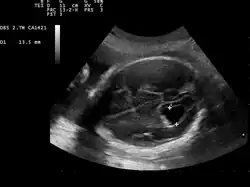

Prenatal ultrasound showing a well defined hypoechoic lesion corresponding to a choroid plexus cyst

Choroid plexus cysts (CPCs) are cysts that occur within choroid plexus of the brain. They are the most common type of intraventricular cyst,[1] occurring in 1% of all pregnancies.[2]

CPCs can form within this structure and come from fluid trapped within this spongy layer of cells, much like a soap bubble or a blister. CPCs are often called "soft signs" or fetal ultrasound "markers" because some studies have found a weak association between CPCs and fetal chromosome abnormalities.